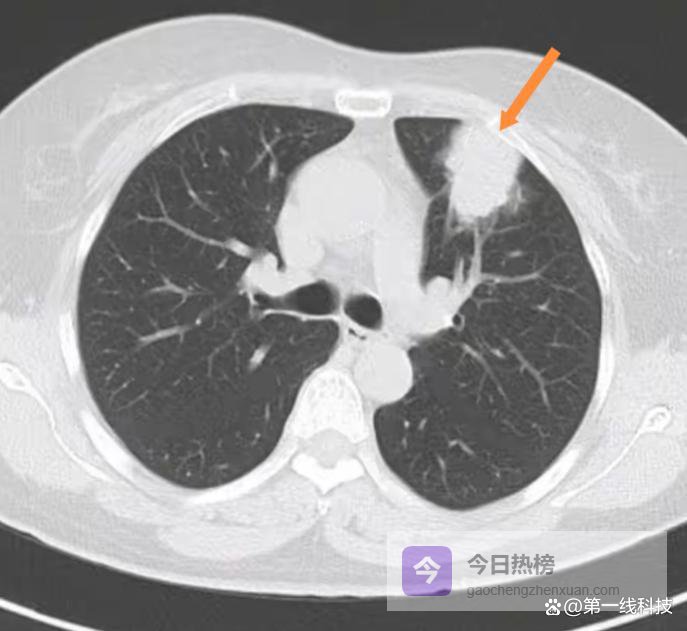

宾夕法尼亚大学和耶鲁大学的团队,在一种特定基因突变(KrasG12D和Trp53缺失)导致的肺腺癌小鼠身上,看到了惊人的一幕。 在高清三维成像下,肺里的肿瘤根本不是孤岛。 它的内部和周围,被密密麻麻的神经纤维穿透、缠绕,像被电网覆盖一样。 这些神经的密度,比旁边健康的肺组织要高得多。

这些神经是哪来的? 追踪发现,它们来自迷走神经。 这是人体最长、分布最广的脑神经,从大脑一路延伸到胸腔、腹腔,主要负责呼吸、心跳、消化这些你不自觉的生理活动。 正常情况下,它是个忠实的“通讯员”,向大脑汇报内脏的感觉。 但现在,它被癌症策反了。

癌细胞是怎么做到的? 它们分泌出神经生长因子之类的物质,就像扔出了一把把“化学钩锁”,主动勾引附近的迷走神经朝自己生长过来。 神经一头扎进肿瘤后,性质就变了。 它的基因表达被重编程,感觉功能和生长相关的基因被显著上调。 它变成了一种带有特殊标记(NPY2R/TRPV1)的“肿瘤特工神经”。